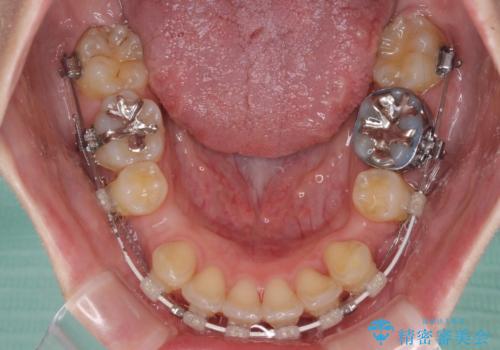

- 審美装置

上下左右第一小臼歯4本を抜歯し、ワイヤー装置にて口元を引っ込めるよう矯正治療を行うこととしました。